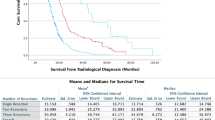

Next, we examined the post-surgery survival of the patients of this cohort. At the time of this analysis, 44 of 70 patients were censored. Across all tumor types and WHO grades, the median survival after repeat surgery was 399 days (Fig. 3B), indicating a median survival long enough for patients to benefit from the personalized targeted therapies that were determined based on the sampled tumor tissue. As expected, patients with WHO grade 4 tumors showed the worst survival after surgery, compared to WHO grade 2 and grade 3 tumors (348 days in WHO grade 4 vs. undefined in other groups, p = 0.03, Gehan-Breslow-Wilcoxon test, Fig. 3C). Indeed, patients with IDH-wildtype GBM conferred a post-surgery survival rate of 334 days. To confirm the prognostic benefit of GTR in the context of this study, we compared survival after repeat surgery in GBM patients undergoing GTR (348 days, n = 34) to that of all other GBM patients (undergoing STR, open or stereotactic biopsies), with undefined survival due to small sample size in the latter (n = 10, p = 0.04, Gehan-Breslow-Wilcoxon test, Fig. 3D).

Although tumor tissue sampling was the primary intention of surgical intervention in this cohort, it was usually not the mere achievement: GTR was possible in 70% of the cases. In our study, patients with IDH-wildtype GBM conferred a median survival after repeat surgery of 348 days (11.6 months) after GTR. This is comparable to survival rates reported in previous trials focusing on GBM patients receiving their first re-resection, which range between 11.9 and 12.9 months [20, 29]. It is important to note that, due to the small sample size and heterogenous treatment regimens, a direct prognostic benefit from the choice of targeted therapy after surgery cannot be deduced in this cohort.

Given the intractable situation of a recurrent glioma without further standard treatment options, patients in this cohort show a considerable post-surgical median survival of about 13 months and about 12 months for GBM patients. This postoperative survival was, according to the data we present, long enough for patients to receive targeted therapy. It has to be noted, however, that 40% of patients with a treatment target identified had deceased before treatment could be commenced, amongst others because of rapid postoperative tumor progression. This observation emphasizes the importance of patient selection.